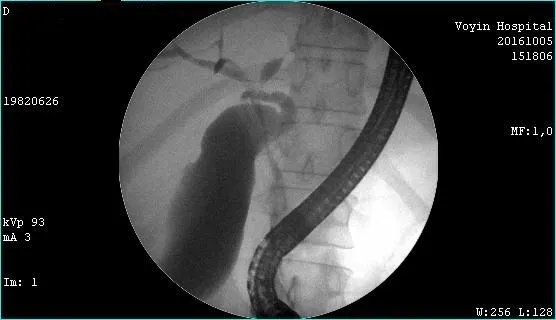

Молодой человек 33 г. Диагноз подтвержден. Стентирован пластиковыми стентами, потом самораскрывающимися. Одномоментно анте и ретроградно - с хорошим результатом. Дальше был поставлен в очередь на трансплантацию. Дальнейшая судьба не известна.